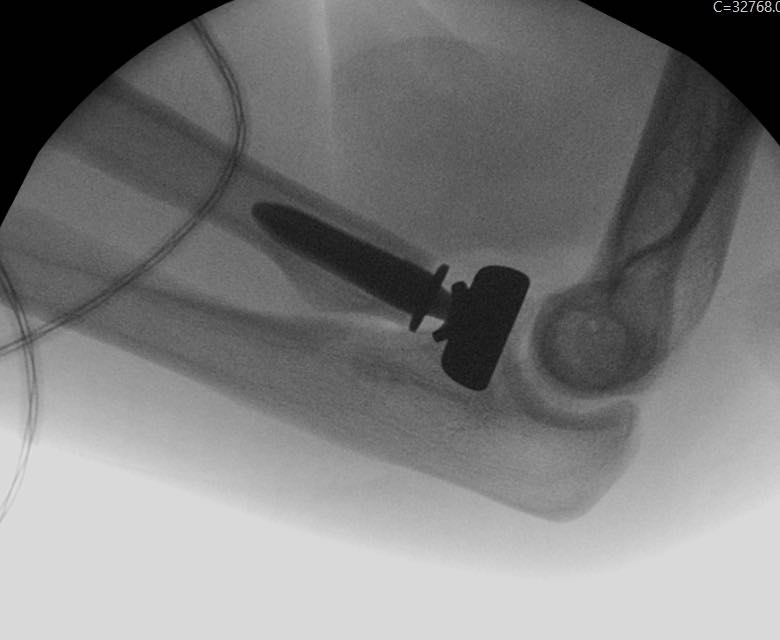

- Fixation or arthroplasty of the radial head

Most terrible triad injuries require surgical management to restore the functionality of your elbow. Surgery involves addressing all the injury components in your elbow. These may include fixation or replacement of the radial head, fixation or suturing of the coronoid and repair of the avulsed ligaments of your elbow.